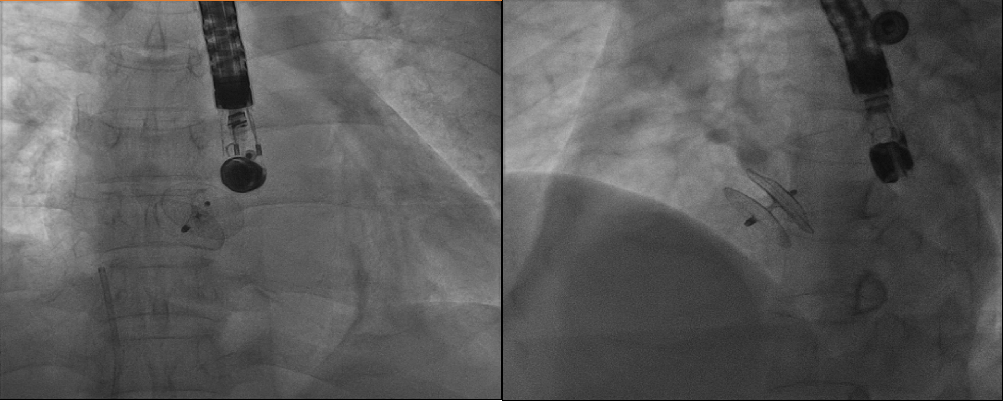

A 48-year-old man was admitted to our hospital with typical symptoms of TIA. Preoperative transesophageal echocardiography demonstrated PFO (Figure 1) and secondary septal pouch on the right (Figure 2, Video 1). Contrast transthoracic echocardiography (TEE) showed a moderate right-to-left shunt (Video 2). To close the secondary septal pouch and the PFO at the same time, successful atrial septal puncture was confirmed under the guidance of TEE (Figure 3A). Subsequently, a 25/25-mm Cera ASD occluder (LifeTech Scientific) was implanted (Figure 4). Post-implantation, the occluder was stable at the implant location (Figure 3B-D). Furthermore, the right-to-left shunt disappeared immediately (Video 3). Thus, ASD occluder implantation may be an effective simultaneous treatment of PFO and secondary septal pouch.

Figure 4. X-ray images showing the occluder’s morphology.